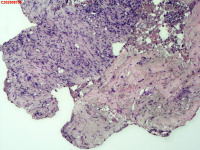

- 右侧胸壁穿刺组织活检

| 性别 | 女 | 年龄 | 81岁 | 临床诊断 | 胸锁关节结核? |

| 一般病史 | 胸部CT示:右肺下叶小结节,建议3-6个月复查,必要时胸外科会诊。左肺上叶多发小斑点、结节影,结核可能。右肺上叶多发点状影。双肺间质性改变。纵隔淋巴结肿大、钙化。右侧胸锁关节见骨质破坏,周围见软组织肿胀。 | ||||

| 标本名称 | 右侧胸壁穿刺组织活检 | ||||

| 大体所见 | B超:体表包块彩超示右侧胸壁混合回声包块,右侧胸壁低回声区,CDFI示:其内未见明显血流信号。 | ||||